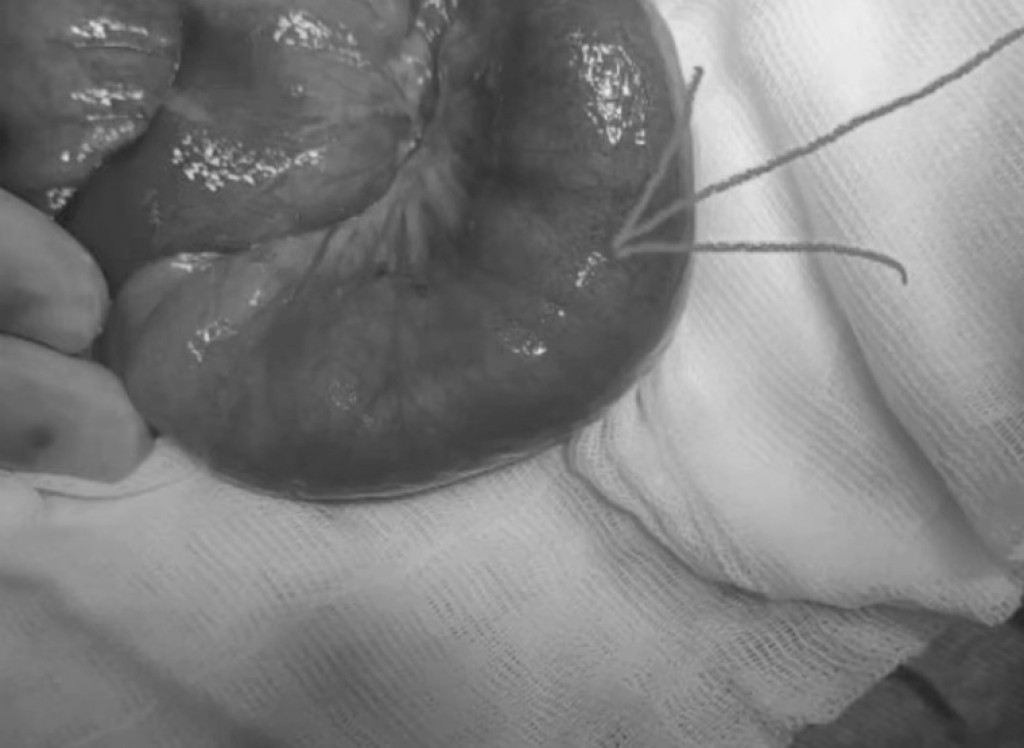

В Караганде медики извлекли комок волос из кишечника 13-летней девочки

Врачи Областной детской клинической больницы извлекли комок волос из тонкого кишечника 13-летней девочки. Пациентка поступила 5 июля, в тот же день ее прооперировали.

"Поступила с клиникой острого аппендицита, интраоперационно обнаружен безоар тонкого кишечника - комок волос", - сообщают в ОДКБ.

В данный момент девочка находится в отделении реанимации. Состояние стабильное, самочувствие не нарушено. Лечение получает в полном объеме.

Медики говорят, что причины, когда ребенок может оказаться в подобной ситуации, бывают разными. Чтобы предотвратить подобное, нужно наблюдать за ребенком и проводить беседы.